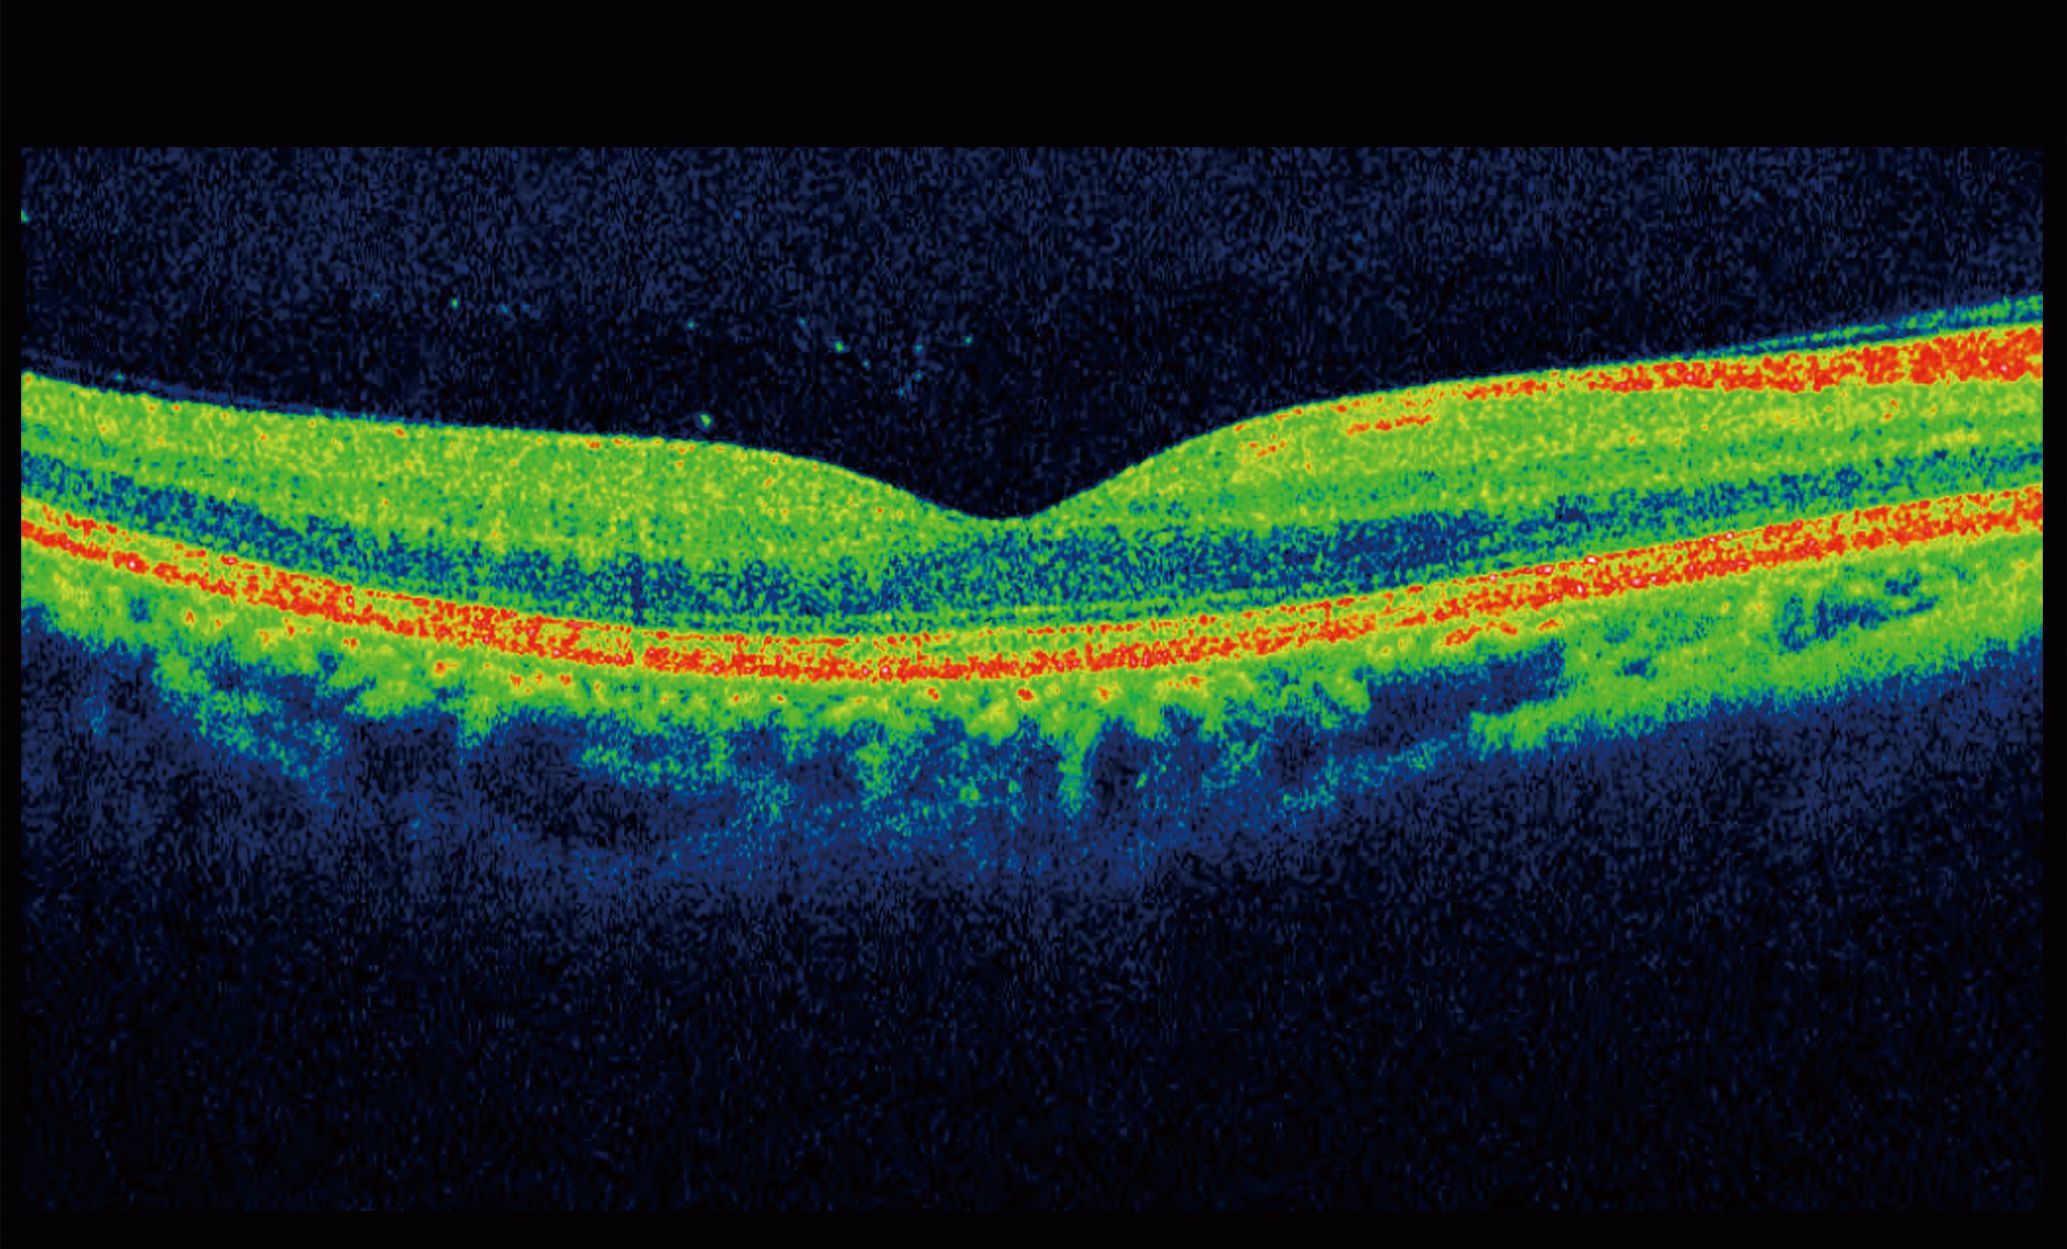

Struggling with painful feet? Discover effective methods for professional big toe callus removal at home. Learn how to safely soften, exfoliate, and treat stubborn skin buildup using pumice stones, moisturizing foot creams, and reliable techniques. Restore comfort and smoothness to your feet today with our expert guide on eliminating uncomfortable pressure points and achieving healthy, soft skin.